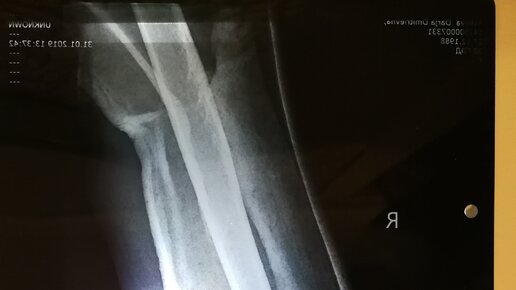

Часть1. Часть2. Утром оказалось что такие травмы сразу не оперируют, а ждут когда спадет отек. Для меня это открытие было дикостью. То есть у меня тут рука, которая ниже локтя держится только на мясе и коже, а чинить меня в ближайшее время никто не собирается. Точнее, во Владимире, как я поняла, меня вообще оперировать не горят желанием. Перелом тяжелый, почти открытый, с осложнениями в виде повреждения лучевого нерва, это когда пальчики на руке висят мертвым грузом и шевелиться не собираются. Никто...

И так, я морально готова говорить о своем переломе нижней трети плечевой кости. Почему решила написать о травме? Когда поломалась, то пыталась найти информацию о похожих случаях травмы в сети, а их там не оказалось, только научные сухие статьи. Сама никогда раньше ничего не ломала, хотелось узнать о реальном опыте людей, как справлялись они. Поняла что многие не представляют каким может быть перелом, считала переломы неприятностью выводящей из строя на месяц-два, не больше. Каталась на сноуборде, в 60км от своего города Владимира, быстро, уверенно, а зря. Словила кантом небольшую кочку и полетела через правую руку...